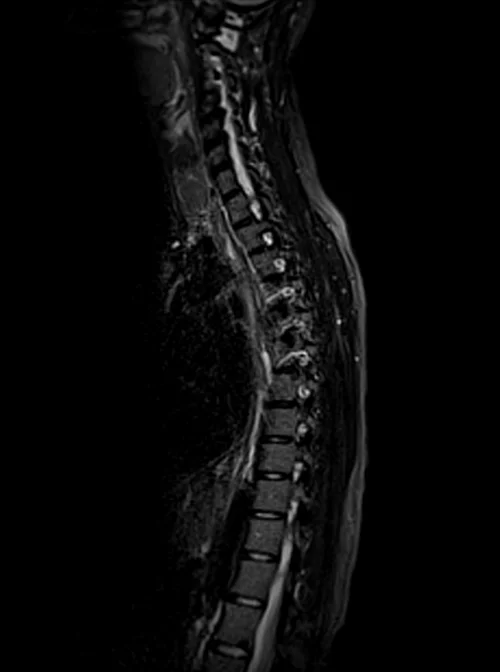

Thoracic spine mri sagittal stir images